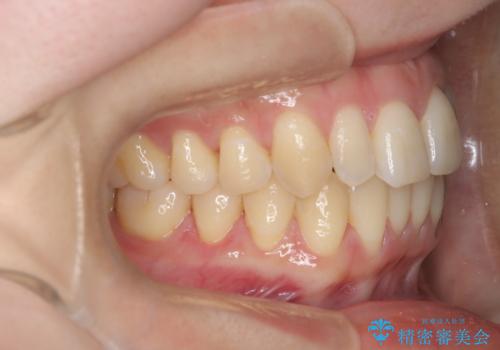

【インビザライン】反対咬合を治したい

- 前歯の反対咬合を主訴に来院されました。

インビザラインにて歯列弓の拡大により叢生の改善を行うことができ、患者様にも満足していただました。

前歯の反対咬合は歯牙への負担も大きくできるだけ早期に治療を行うことを推奨しています。